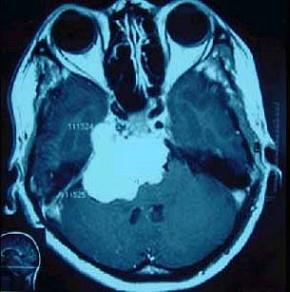

问题 下面哪些符合脑膜瘤(如图所示)表现()

选项 A.脑膜瘤起病慢、病程长,可达数年之久 B.初期症状及体征不明显,以后逐渐出现颅内高压征及局部定位症状及体征 C.颅内高压征的出现通常提示瘤体已较大或肿块阻塞了脑脊液通道 D.局部定位征象因肿瘤所在部位而异 E.脑膜瘤起源于蛛网膜细胞丛,与蛛网膜颗粒关系密切

答案 ABCDE